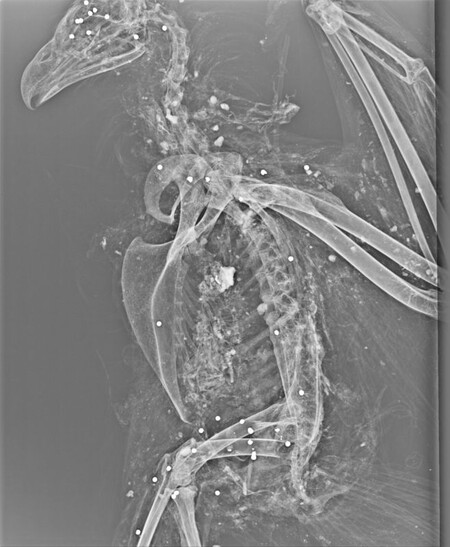

„To, že mrtvý pták neměl pařáty, by mohlo nasvědčovat tomu, že byl chycen do želez a následně zastřelen. Domníváme se proto, že mohl být spáchám trestný čin týrání zvířete zvláště surovým nebo trýznivým způsobem. Podali jsme trestní oznámení na neznámého pachatele a požádali policii, aby nás informovala o průběhu vyšetřování. Mrtvý pták byl zhruba čtyřletý, to znamená, že se už mohl rozmnožovat a posílit tak zdejší populaci,“ vysvětluje Vlastimil Sajfrt z Agentury ochrany přírody a krajiny ČR.